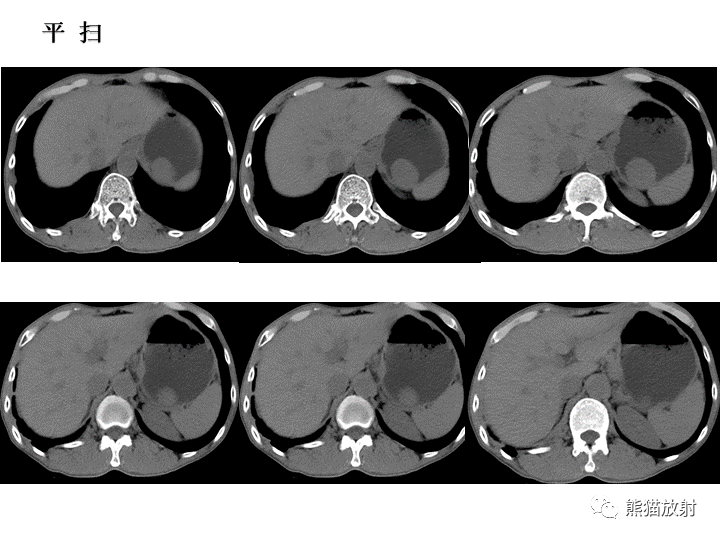

【病例】胃间质瘤VS神经鞘瘤-1